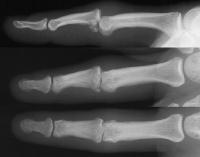

This gentleman sustained a comminuted proximal interphalangeal fracture dislocation.

The palmar base of the middle phalanx is in at least three thin fragments. The palmar ulnar condyle of the proximal phalanx head has irregular sections of cartilage loss.